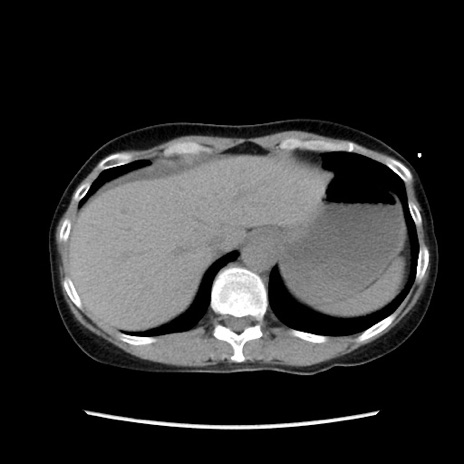

症例32(横断像)

【症例】40歳代 女性

【主訴】上腹部痛、嘔気・嘔吐

【現病歴】約9時間前頃から急に上腹部痛、嘔気、嘔吐が出現。改善しないため救急要請。

【既往歴】子宮頚癌(広汎子宮全摘術、放射線療法)、腸閉塞

【身体所見】腹部:平坦、軟、腸雑音亢進、上腹部を中心に腹部全体に圧痛あり。

【データ】WBC 8400、CRP 0.03